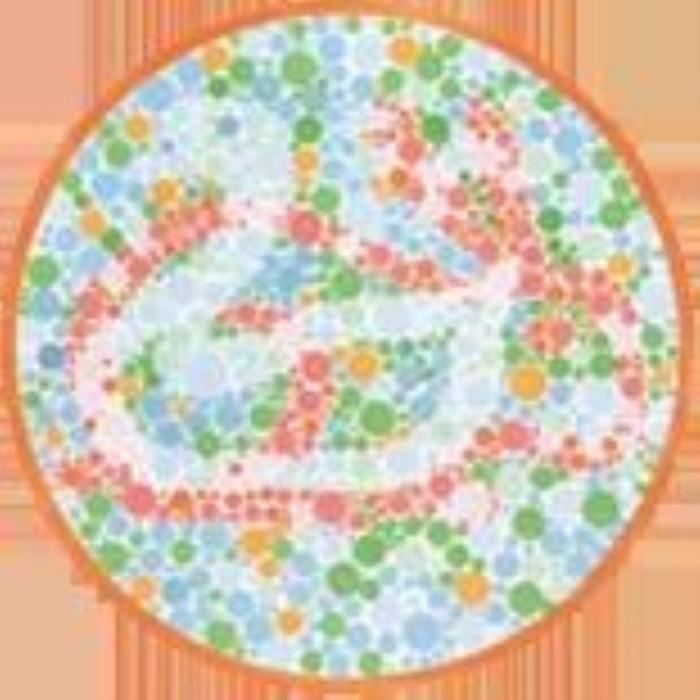

(正常 绿色盲 红色盲 蓝黄色盲)

(正常 绿色盲 红色盲 蓝黄色盲)

根据不同类型的色盲,以及色盲的严重程度,患者多少是能看到一些颜色的,或者说只是有些颜色看起来跟常人不同,但并不等于是“黑白”的世界。